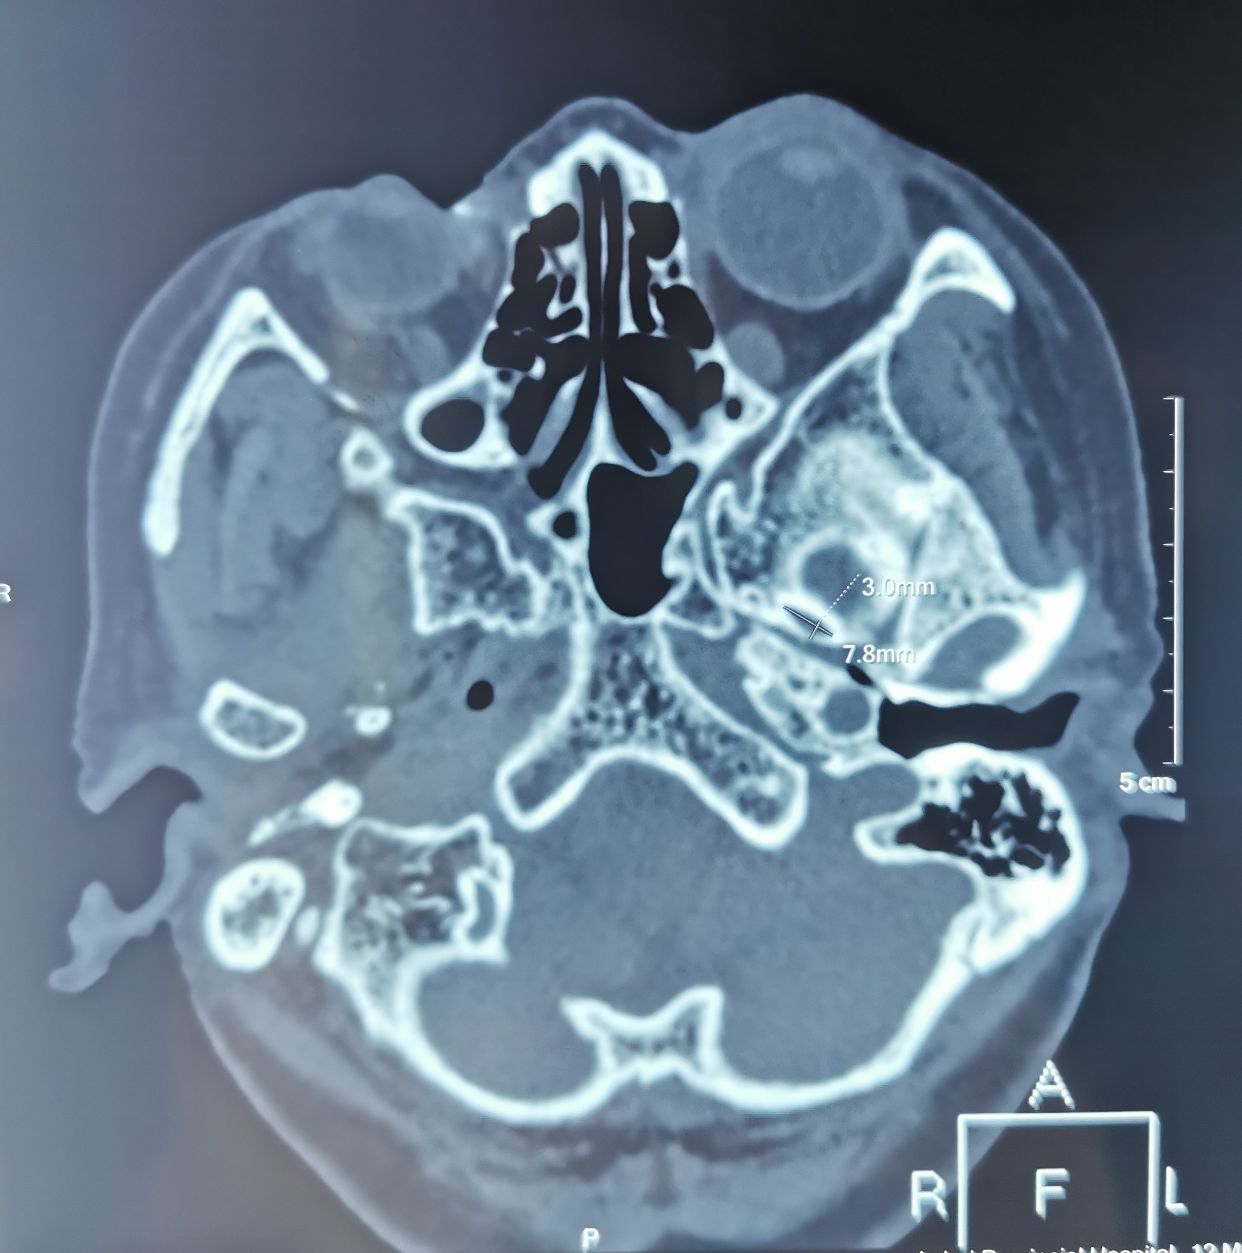

女性,66岁,左侧三叉神经痛

基础疾病多,无法MVD手术,选择PBC

左侧卵圆孔内侧狭小